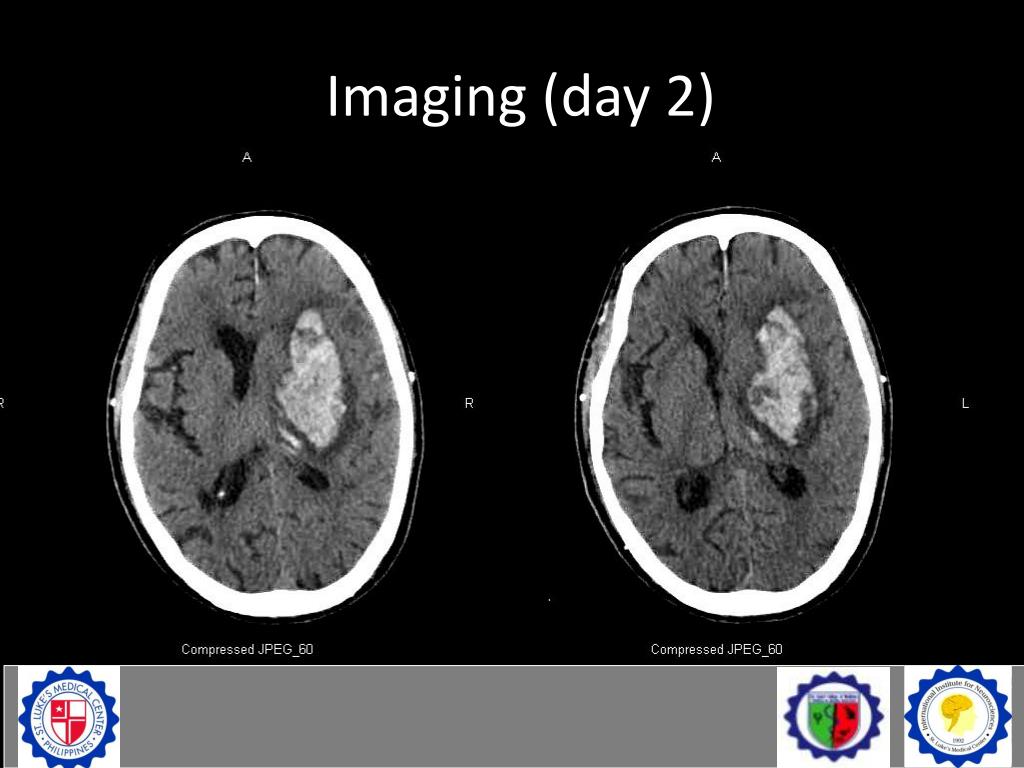

19. Imaging (day 2)

20. Imaging (day 2)

21. Imaging (day 2)

22. Imaging (day 2) • Interval evolution to beginning subacute stage • Without increase in volume • Interval progression of perilesional edema • Midline shift to the right has not significantly changed